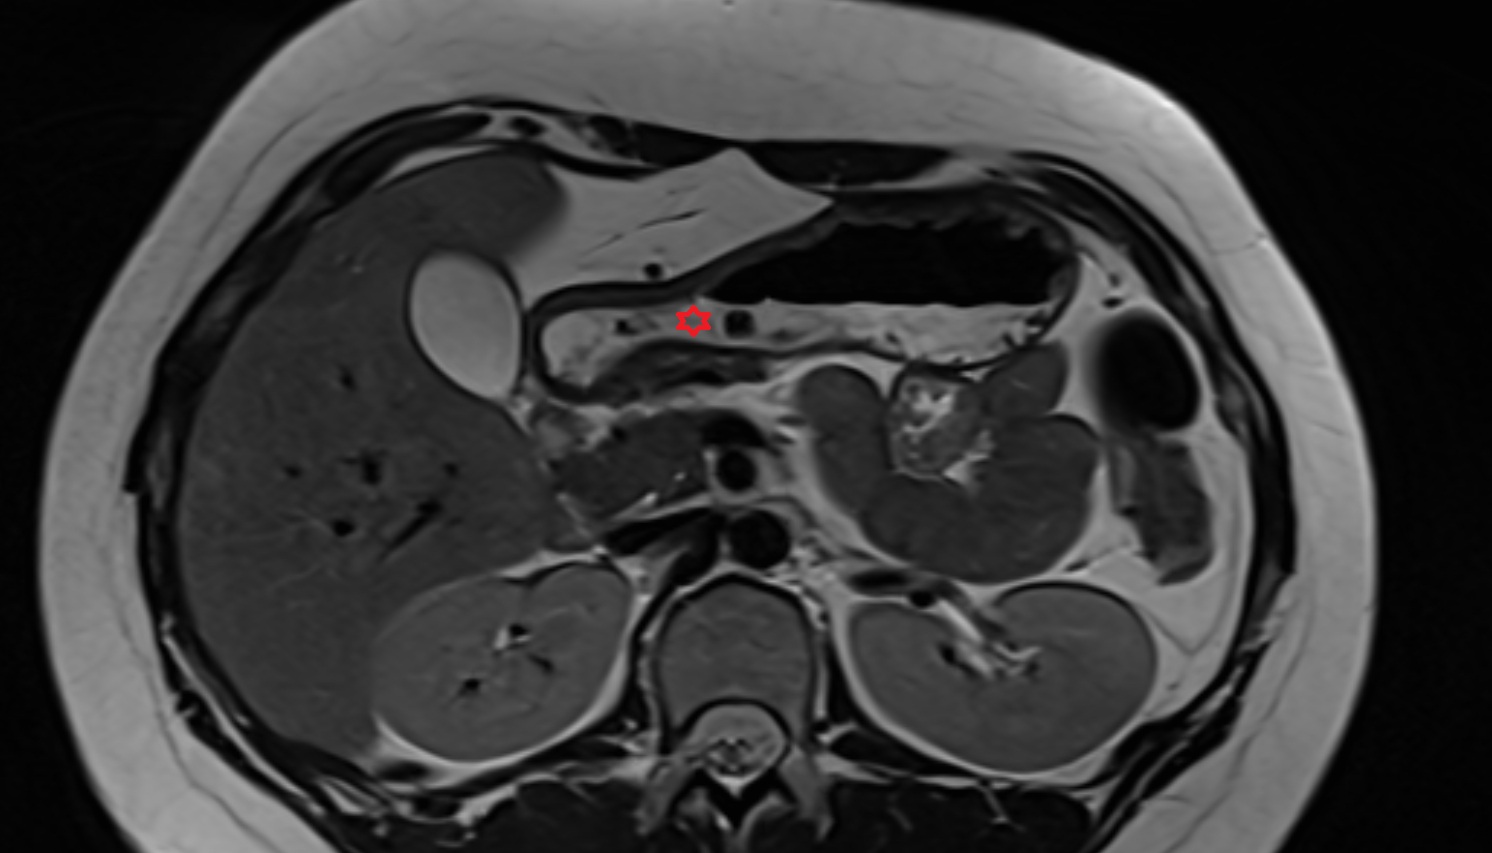

- kidneys

- Right kidney

- Left kidney

- Kidney cortex (Renal cortex)

- Renal capsule

- Renal medulla

- Renal pyramids

- Renal artery

- Renal vein

- Renal pelvis